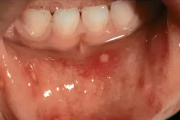

Lapse stomatiit

Tekitajad ja kliiniline pilt Gingivostomatiit – Tekitaja herpessimplex-viirus – Primaarinfektsioon, mille üldnähtudeks on palavik, halb enesetunne ja peavalu. – Herpeseville leidub põskede limaskestal, huultel ja keelel, sageli lõhkevad need kiiresti ja jätavad väikese erosiooni. – Loe edasi »